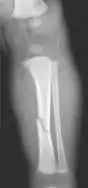

The material factual allegations of the amended complaint are as follows. Plaintiff was born on May 14, 1970. On repeated occasions during the first year of her life she was severely beaten by her mother and the latter's common law husband, one Reyes. On April 26, 1971, when the plaintiff was eleven months old, her mother took her to the San Jose Hospital for examination, diagnosis, and treatment. The attending physician was defendant Dr. Flood, acting on his own behalf and as agent of the defendant San Jose Hospital. At the time, the plaintiff was suffering from a comminuted spiral fracture of the right tibia and fibula, which gave the appearance of having been caused by a twisting force. Plaintiff's mother had no explanation for this injury. Plaintiff had bruises over her entire body. In addition, she had a non-depressed linear skull fracture which was then in the process of healing. Plaintiff demonstrated fear and apprehension when approached. Inasmuch as all plaintiff's injuries gave the appearance of having been intentionally inflicted by other persons, she exhibited the medical condition known as the battered child syndrome.

It is alleged that proper diagnosis of plaintiff's condition would have included taking X-rays of her entire skeletal structure, and that such procedure would have revealed the fracture of her skull. Defendants negligently failed to take such X-rays, and thereby negligently failed to diagnose her true condition. It is further alleged that proper medical treatment of plaintiff's battered child syndrome would have included reporting her injuries to local law enforcement authorities or juvenile probation department. Such a report would have resulted in an investigation by the concerned agencies, followed by a placement of plaintiff in protective custody until her safety was assured. Defendants negligently failed to make such report.